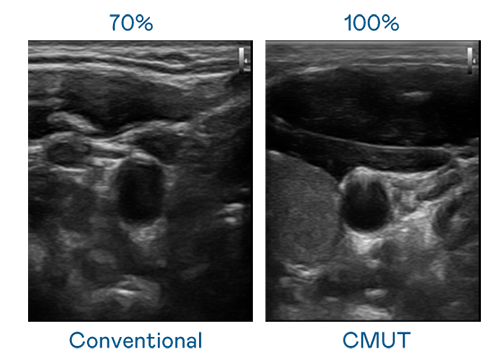

CMUT 技术是一种用电容式微机电元件来产生超音波讯号的技术。与传统 PZT 压电式技术相比,CMUT 频宽增加 30%,更宽频的超音波讯号让影像解析度大幅提升,是实现高影像品质医疗超音波扫描、促进精准医疗发展的关键技术。

超音波影像的解析度高低,首先取决于探头能发出的讯号频宽。PA旗舰厅 CMUT 可提供高清晰的超音波讯号,提供高频宽、高灵敏度、影像纹理细节更高的超音波影像,协助医护人员缩短影像判读时间及利用精准的医疗影像进行诊断。